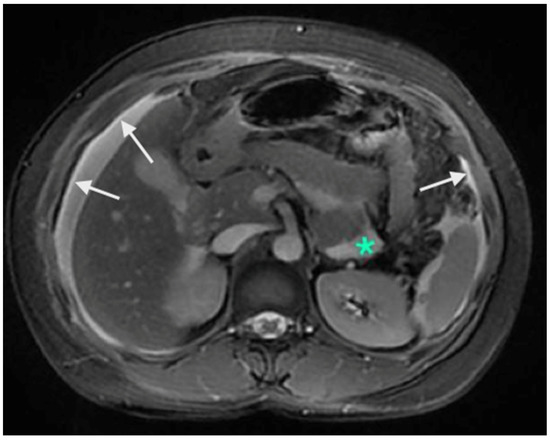

5. Preoperative Imaging

- Low, R.N.; Barone, R.M.; Lucero, J. Comparison of MRI and CT for predicating the peritoneal cancer index (PCI) in patients being considered for cytoreductive surgical procedures. Ann. Surg. Oncol. 2015, 22, 1708–1715. [Google Scholar] [CrossRef] [PubMed]

- Dohan, A.; Hoeffel, C.; Soyer, P.; Jannot, A.S.; Valette, P.J.; Thivolet, A.; Passot, G.; Glehen, O.; Rousset, P. Evaluation of the peritoneal carcinomatosis index with CT and MRI. Br. J. Surg. 2017, 104, 1244–1249. [Google Scholar] [CrossRef]

- Low, R.N.; Barone, R.M.; Rousset, P. Peritoneal MRI in patients undergoing cytoreductive surgery and HIPEC: History, clinical applications, and implementation. Eur. J. Surg. Oncol. 2021, 47, 65–74. [Google Scholar] [CrossRef] [PubMed]